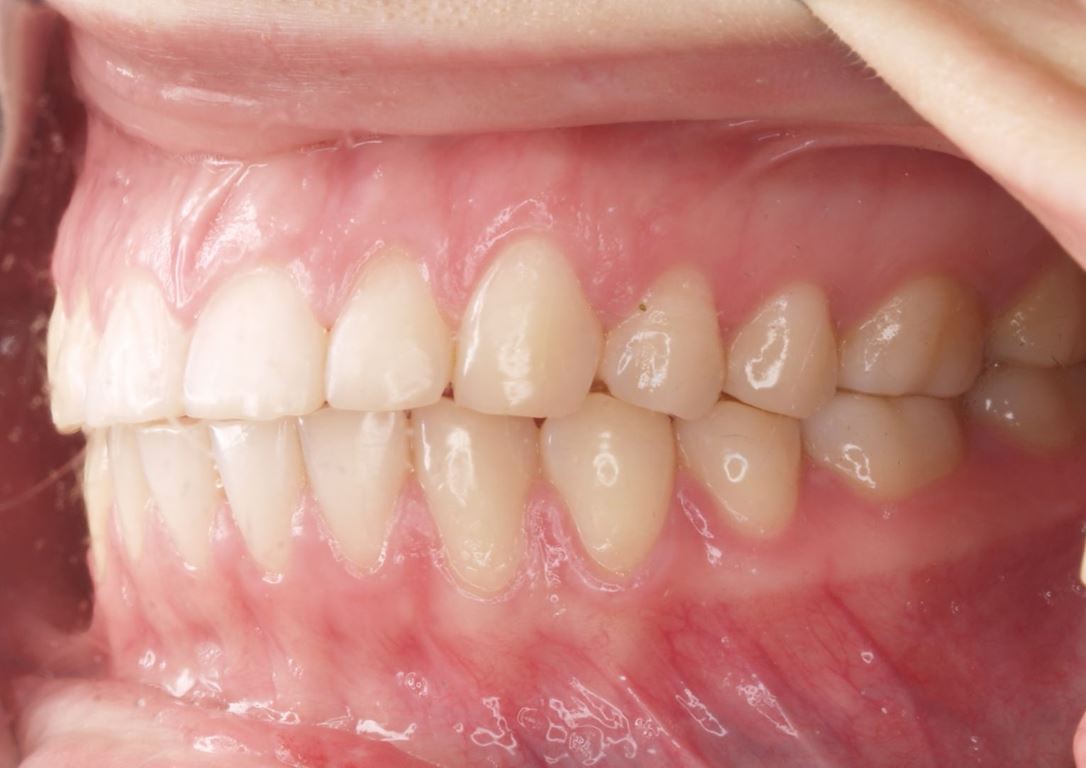

W pierwszym etapie diagnostycznym wykonano zdjęcia zewnątrz- i wewnątrzustne (ryc. 1-12).

Ryciny 39-50 przedstawiają stan po zakończeniu leczenia.